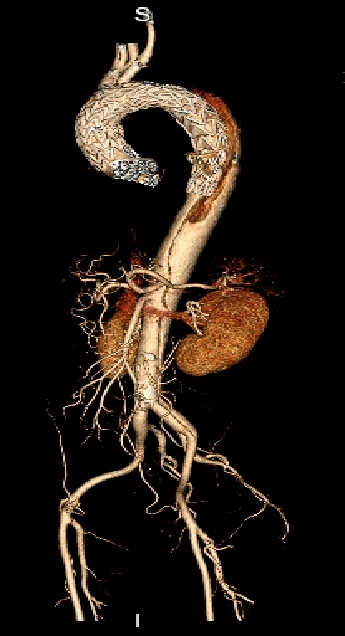

男性,44岁,慢性B型夹层。2010年12月行TEVAR术。

2013年5月发现RTAD,未处理。2015年2月死亡。

▎病例二

男,52岁,慢性夹层。2015年8月入院,4年前曾因B型层行TEVAR术,主动脉解剖变异,扭曲。行双烟囱+TEVAR术。术后第3天RTAD ,死亡。

▎病例三

男,60岁,慢性夹层。2013年12月行Debranching+TEVAR术 。2016年7月复查: RTAD ,未手术。失访。

▎病例四

男, 49岁,急性夹层 。2018年11月TEVAR。一月后复查:RTAD 。 2019年1月双开窗。2019年4月2日 复查,结果良好。